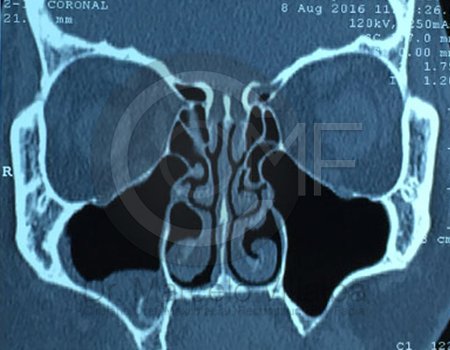

Antes de la extracción se realiza una valoración clínica y estudios de imagen, como radiografías panorámicas o tomografías, para conocer la posición del tercer molar, su relación con los nervios y planificar un procedimiento seguro y adecuado para cada paciente.

Es una conexión entre la cavidad oral y el seno maxilar que puede ocurrir tras extracciones o infecciones. Su tratamiento busca cerrar adecuadamente la comunicación para evitar molestias e infecciones sinusales.